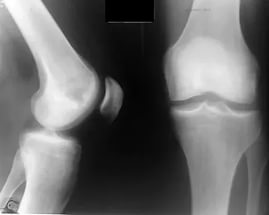

Правосторонний гонартроз 2 степени

Пациентке в многопрофильной клинике №1 Витерра Беляево была проведена рентгенография правого коленного сустава. По данным рентгенографии, диагностирован Деформирующий остеоартроз правого коленного сустава.

После клинического и рентгенологического исследования, диагностирован - Правосторонний гонартроз 2-й степени.